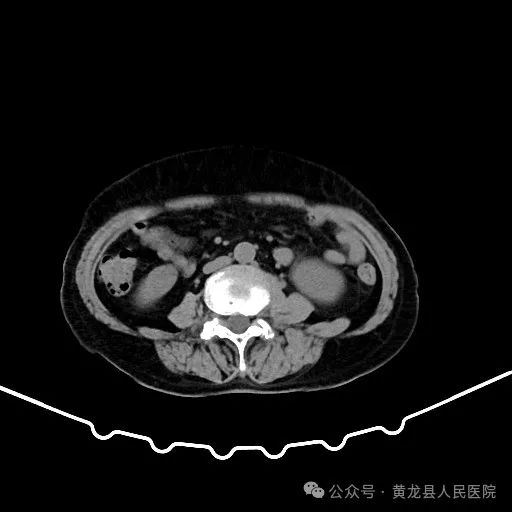

双肾增强CT

患者男性,70岁,因“发现右肾肿物1年余”收住于我院外科,经查体及相关检查后诊断为:右肾肿瘤。为尽早解除患者疾病困扰,方继荣主任迅速组织泌尿外科、手麻科、普外科等多学科进行会诊,对患者的病情进行了全面而深入的评估。最终确定详细周密手术方案,将患者病情及治疗方法告知患者及家属征得同意后,由我院泌尿外科刘涛主治医师实施手术。